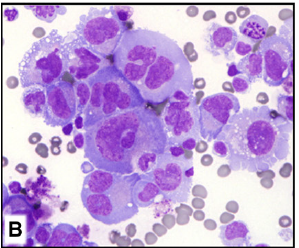

Anaplastic large cell lymphoma (ALCL), ALK positive

Anaplastic large cell lymphoma (ALCL), ALK negative